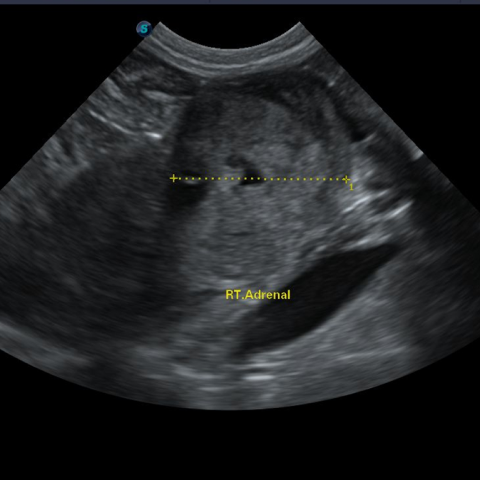

Á¤»ó ÁÂÃø ºÎ½Å

¿ìÃø ºÎ½Å ºñ´ë